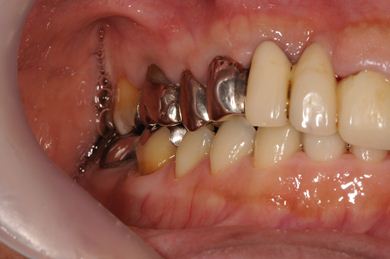

インプラントの症例写真 IMPLANT

抜歯即日スピードインプラント治療

| 治療内容 | インプラント2本(抜歯即日スピードインプラント)、ハイブリッドセラミック2本 | ||||||||||||||||||||||||||||||||